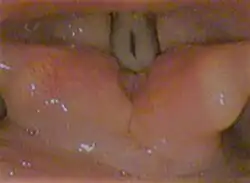

Laryngoscopic view of the vocal folds.